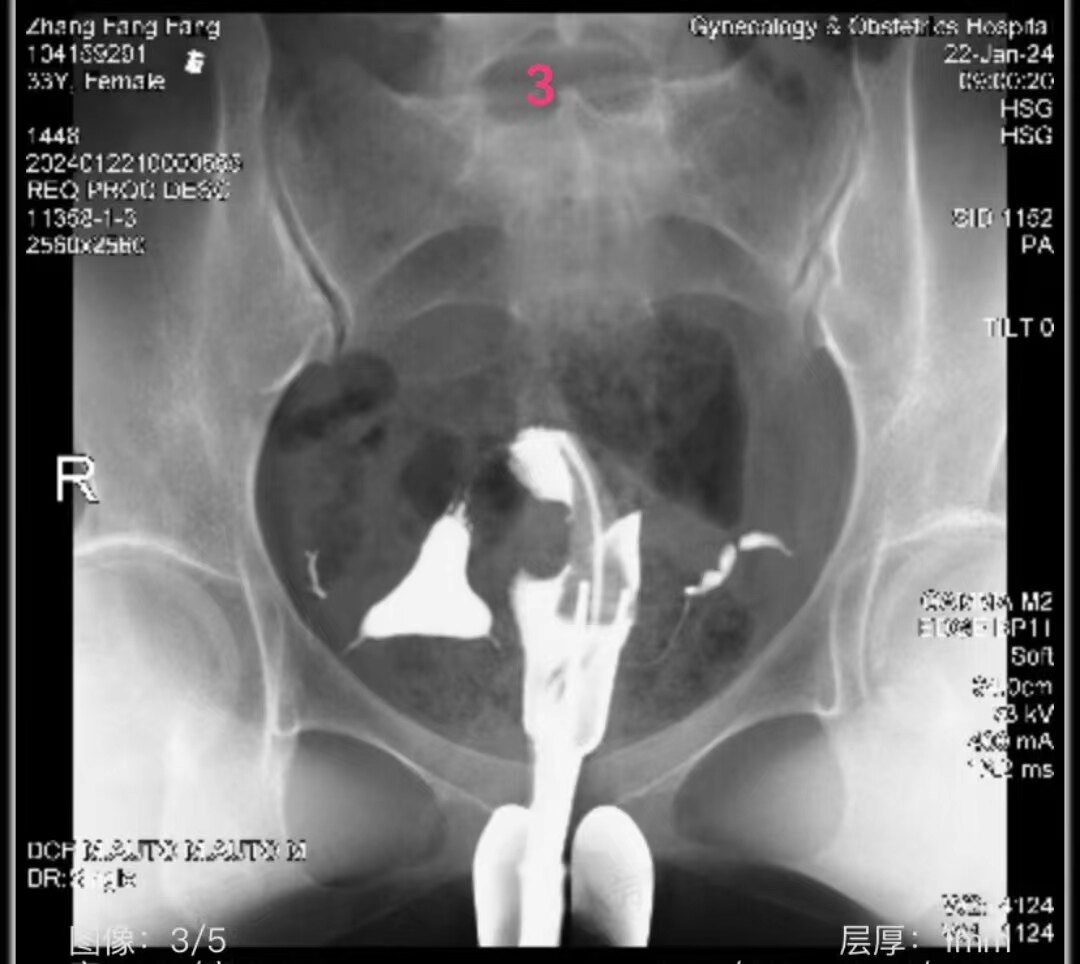

33.jpg

左侧输卵管显影至壶腹部远端,右侧输卵管显影至壶腹部近段。造影剂返回到阴道

3.jpg